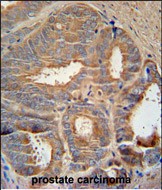

- AZGP1 Antibody (N-term) (Cat. #P30381) immunohistochemistry analysis in formalin fixed and paraffin embedded human prostate carcinoma followed by peroxidase conjugation of the secondary antibody and DAB staining. This data demonstrates the use of the AZGP1 Antibody (N-term) for immunohistochemistry. Clinical relevance has not been evaluated.